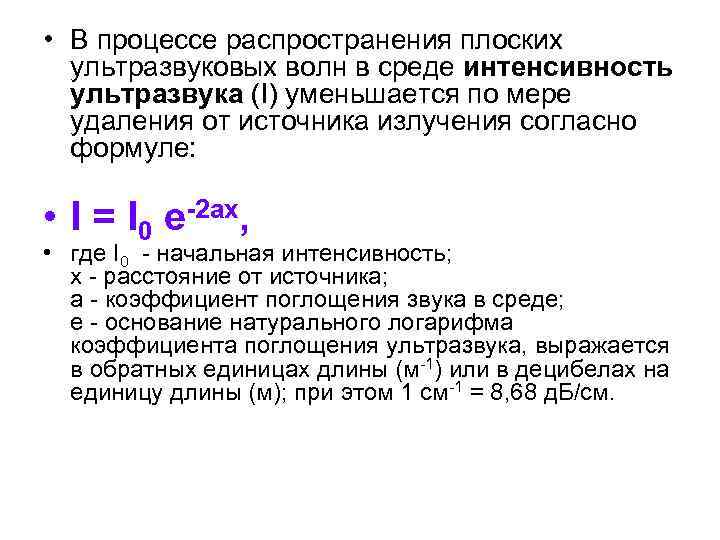

• В процессе распространения плоских ультразвуковых волн в среде интенсивность ультразвука (I) уменьшается по мере удаления от источника излучения согласно формуле: • I = I 0 e-2 ax, • где I 0 - начальная интенсивность; x - расстояние от источника; а - коэффициент поглощения звука в среде; е - основание натурального логарифма коэффициента поглощения ультразвука, выражается в обратных единицах длины (м-1) или в децибелах на единицу длины (м); при этом 1 см-1 = 8, 68 д. Б/см.

• В процессе распространения плоских ультразвуковых волн в среде интенсивность ультразвука (I) уменьшается по мере удаления от источника излучения согласно формуле: • I = I 0 e-2 ax, • где I 0 - начальная интенсивность; x - расстояние от источника; а - коэффициент поглощения звука в среде; е - основание натурального логарифма коэффициента поглощения ультразвука, выражается в обратных единицах длины (м-1) или в децибелах на единицу длины (м); при этом 1 см-1 = 8, 68 д. Б/см.